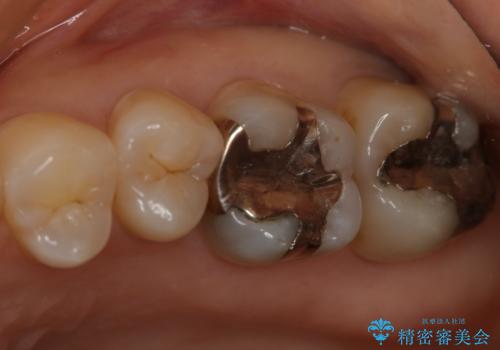

- 左上6番の銀歯をセラミックにしたいと希望され来院された患者様です。

切削量を考慮し、セラミックインレーを選択しました。

銀歯を除去したところ虫歯が深かったので、CRを詰めた上で形態を整えています。